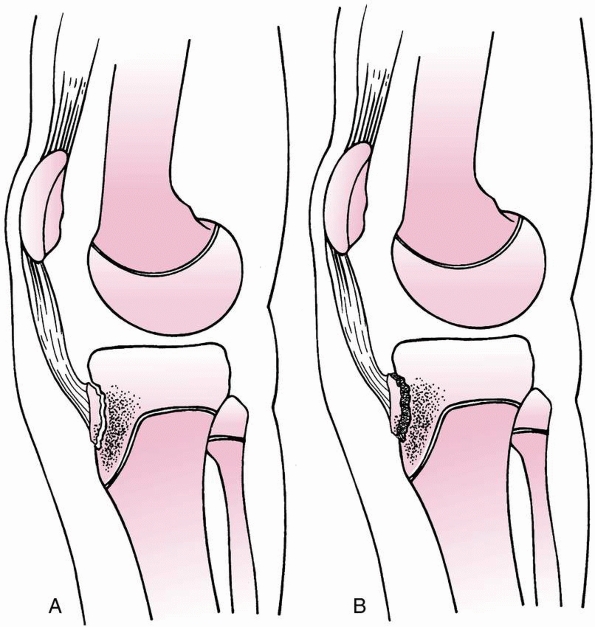

FIGURE 23-11 A. Distal femoral physeal separation prior to the age of 2 years may not disrupt growth because the physis is flat. B.

After the age of 2 years, a central ridge and four quadrants of undulation develop in the distal femur. Fractures in this age group are more likely to cross multiple planes of bone and cartilage. |

satisfactory outcomes,95,133,159 possibly because epiphyseal undulations and the central peak are not as prominent in infants as in older children (Fig. 23-11A).111

In juveniles and adolescents, the fracture may pass through the central

prominence and lead to central growth arrest due to interference with

vascularity in this region or due to the fracture plane exiting and

re-entering the central physis (Fig.23-11B).111,133,151